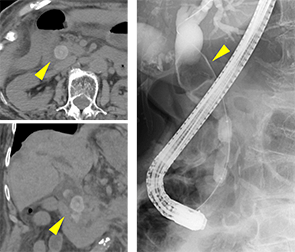

総胆管結石や悪性腫瘍(膵癌、胆道癌)などによって胆道の流れが滞り、黄疸や感染がみられる場合はプラスチックや金属性のステントを胆管に挿入して胆汁の流れをよくします。

膵癌による胆管狭窄

胆管ステント留置後

超音波内視鏡検とは、内視鏡の先端に取り付けられた超音波画像装置で、膵臓、胆嚢、胆管、リンパ節などの通常の腹部エコー、CT、MRIなどの検査で見にくい部位を調べることができる検査法です。

詳細な観察に関してはEUSが一番優れており、CTやMRIでは発見できないような小さな膵癌を発見することができます。

CT、MRIで膵管狭窄はある

が腫瘤は指摘できず

超音波内視鏡のみで

膵管狭窄部に膵腫瘤を指摘